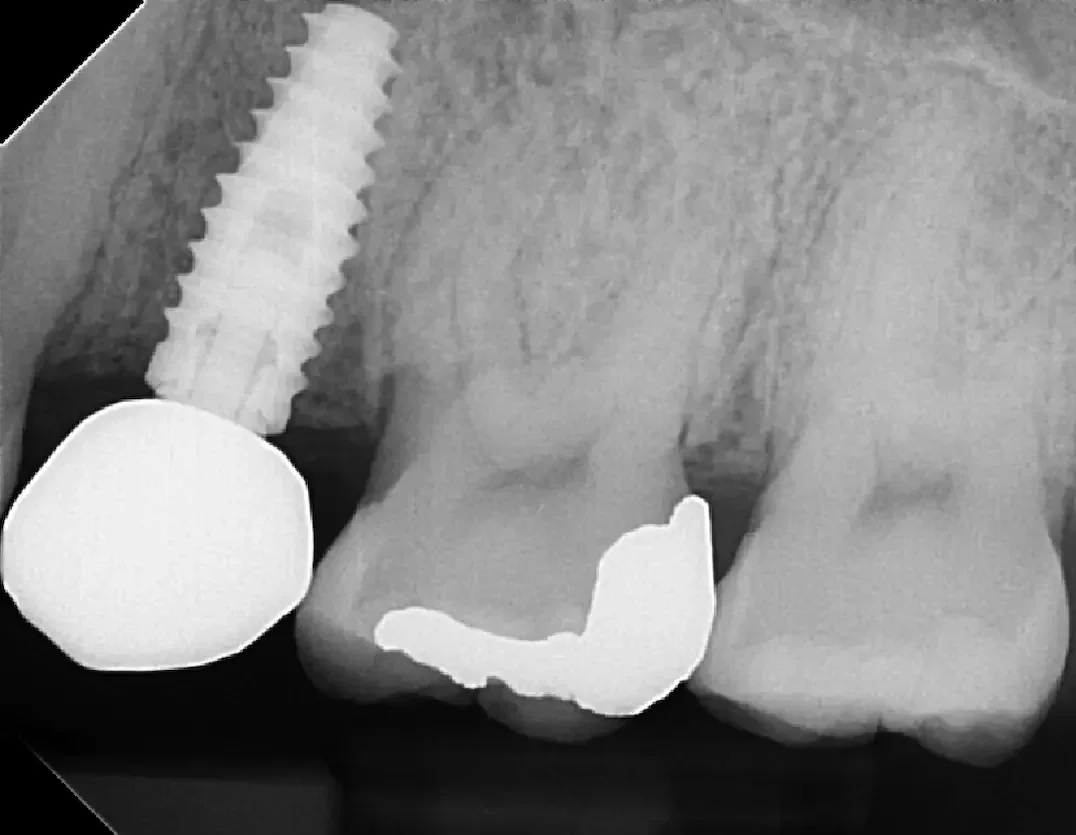

👀 Step 1: Pre-Op Evaluation

Before removing the tooth, we assessed bone health and root position with detailed imaging. In this case, the tooth had a prior root canal and a cavity on the back side, which caused the crown to loosen and eventually fall off. This tooth could not be saved by a new crown, so it needed to be extracted to prevent risk of infection and further damage of surrounding tissue. After reviewing alternative options, this patient is planning on a future dental implant to restore the site.

Images:

X Ray of tooth #18 Prior to Extraction

✅ Purpose: understand root formation, nerve anatomy, and ensure the socket walls are intact for grafting.